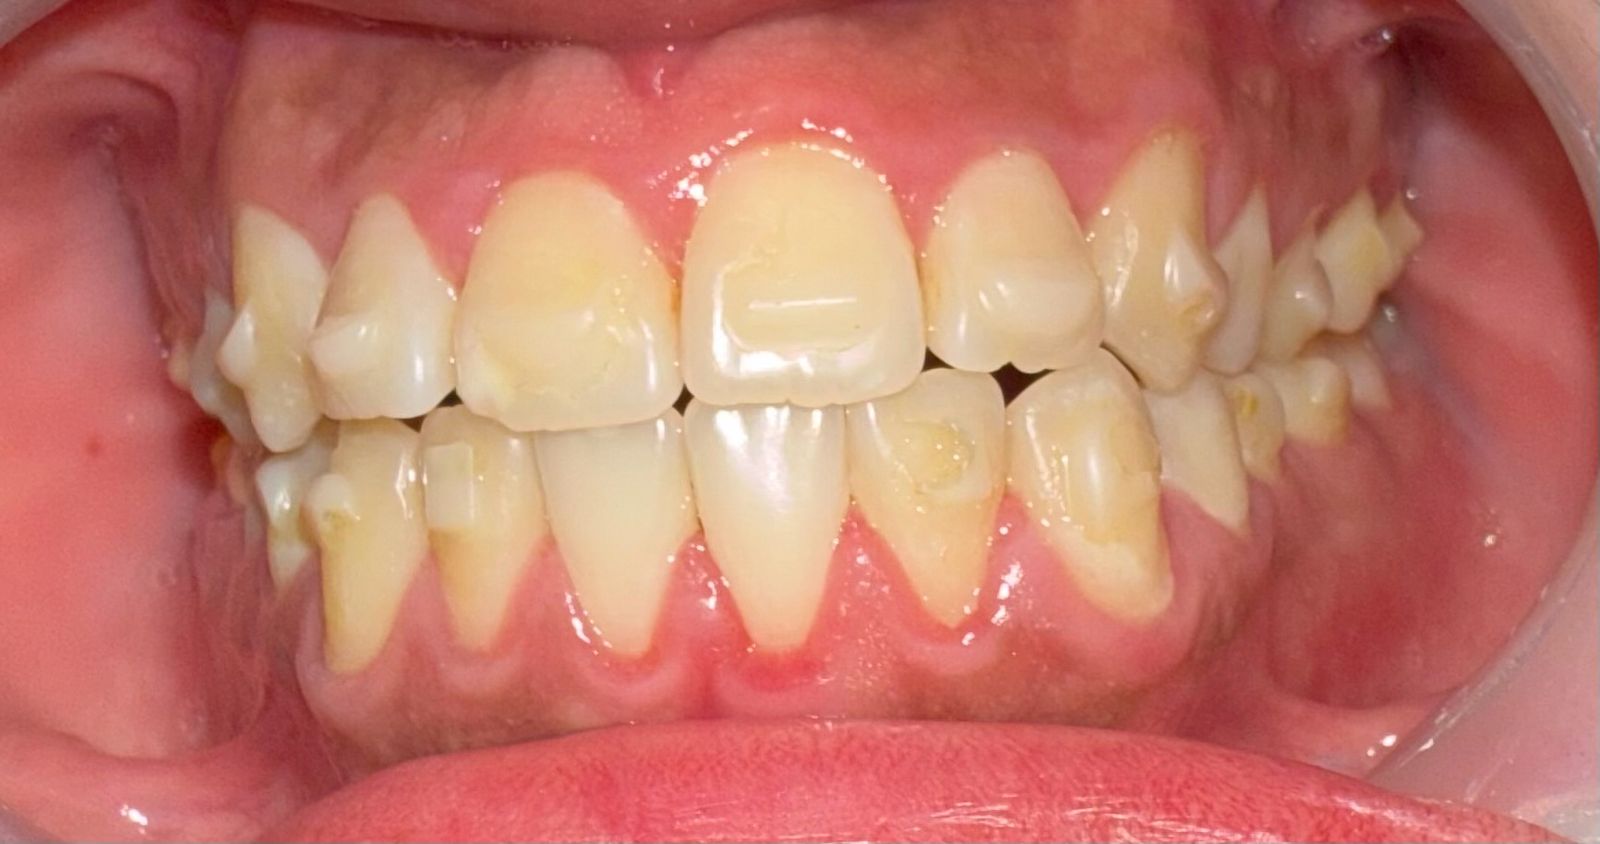

Before & After Results

At Aline Dent, we take pride in delivering visible and lasting improvements in our patients’ smiles. Our before-and-after results highlight the effectiveness of modern dental treatments combined with personalized care. This gallery showcases real dental cases treated at our clinic, giving you a clear idea of how different dental concerns can be corrected with the right treatment approach.

From minor corrections to complete smile enhancements, these teeth transformation results demonstrate how professional dental care can improve both oral health and appearance. Our experienced dental team carefully evaluates each patient’s needs and creates customized treatment plans to achieve natural, healthy, and confident smiles.

In this gallery, you will find a variety of smile makeover cases, including treatments for crooked teeth, gaps, discoloration, damaged teeth, and other common dental concerns.